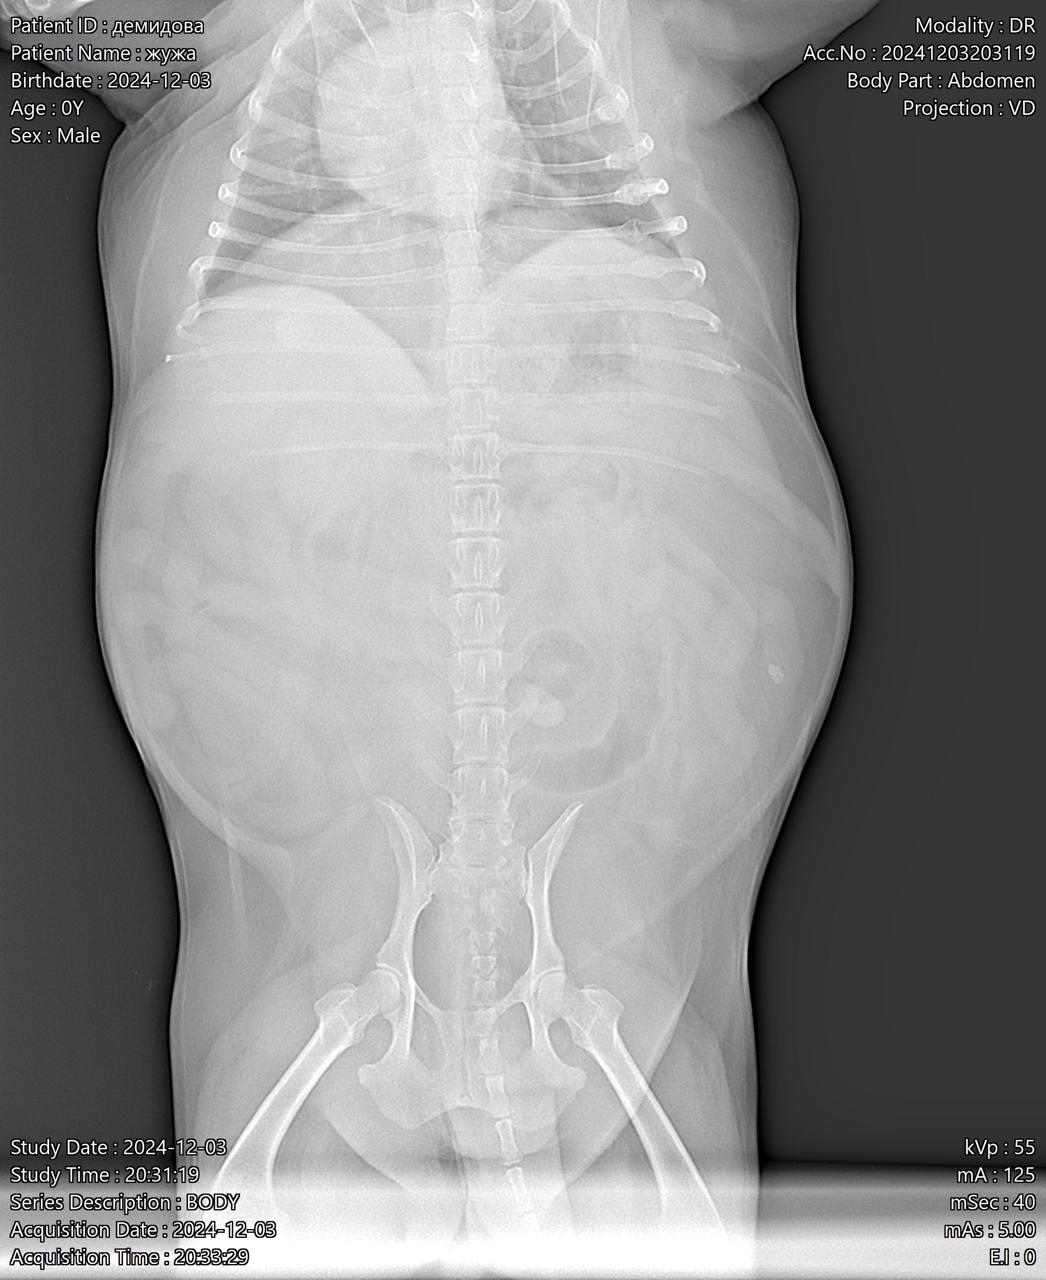

Визит к врачу с поносом